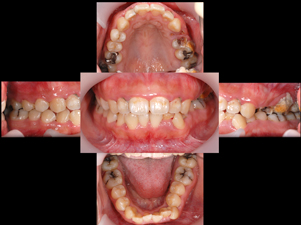

歯周病治療

しっかりと治療を行い、

健全な歯肉を取り戻しましょう。

歯周病は進行すればするほど治療が難しく費用もかかってしまいます。もちろん歯周病にならないように日々のケアをすることはとても大切ですが、万が一歯周病が進行してしまった際も、できる限り早めの処置で歯を抜かなくて済む場合もございます。

まずは当院にご相談ください。

症例1

Before

After

- POINT

- 20代前半の患者様です。年齢が若くても歯周病、歯肉炎は発症してしまいます。ホームケアの指導と治療の説明をしっかり行い、専門家によって丁寧に歯石を除去することで、健康な歯茎を取り戻しました。前歯の厚い歯茎は歯茎の形態を整える手術をしています。すべて保険治療です。